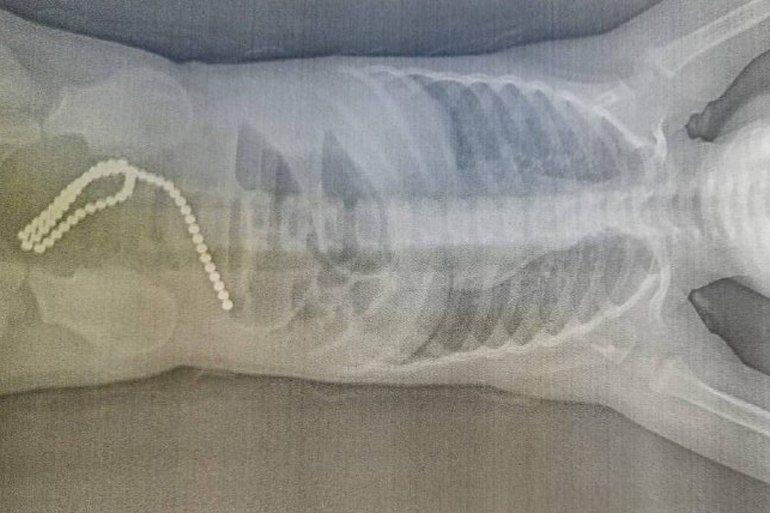

В ходе диагностики были обнаружены инородные тела в кишечнике — 60 маленьких магнитных шариков. Такие элементы входят в состав развивающих детских игр. Девочка играла с яркими магнитами, родители на какой-то момент отвлеклись. Ребёнок наглотался инородных тел.

— Это очень опасно: если случайно проглотить несколько магнитов, они могут сгруппироваться в желудочно-кишечном тракте и вызвать сдавливание стенки кишечника. Это может привести к некрозу, перфорации, закупорке кишечника, образованию свищей и завороту кишечника. У девочки инородные тела вызвали кишечную непроходимость и повреждение стенок кишечника, — рассказал заведующий детским хирургическим отделением, детский хирург высшей квалификационной категории Андрей Костенко.